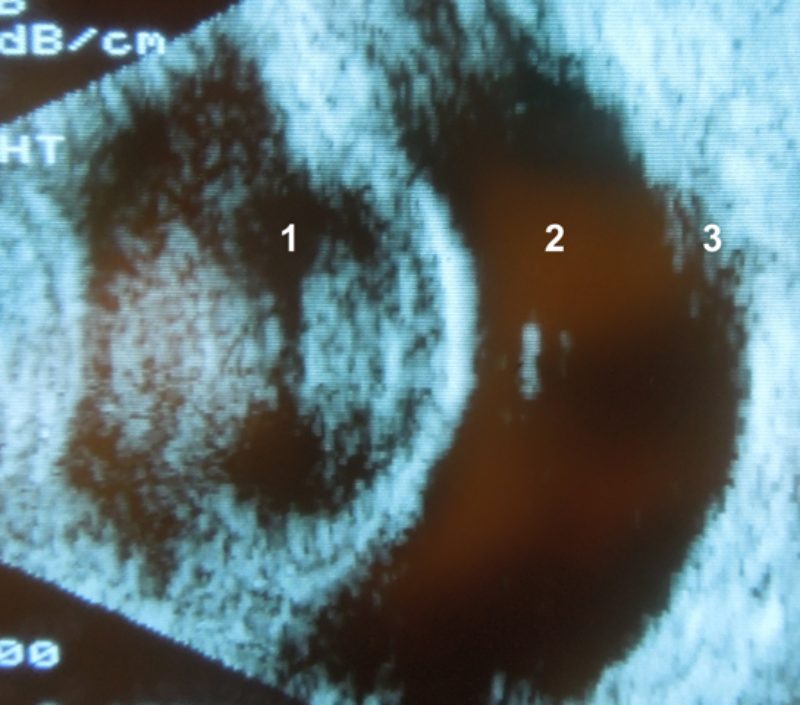

Augenultraschall vor der Operation

Vor der Operation muss ein Augenultraschall durchgeführt werden. Durch die trübe Linse kann der hintere Augenabschnitt bei der Augenuntersuchung nicht mehr gesehen werden. Mittels Augenultraschall ist eine Beurteilung aber möglich und vor der Operation unerlässlich. Bei der Untersuchung geht es vor allem darum, Veränderungen zu erkennen, die die Operation beeinflussen können oder einer OP sogar entgegenstehen. Beispielsweise darf die Netzhaut nicht abgelöst sein. Von Interesse ist auch, ob die hintere Linsenkapsel intakt oder eingerissen ist. Besonders bei den schnell entstehenden diabetogenen grauen Staren kann es zu einem Riss in der Linsenkapsel kommen. Dies betrifft vor allem die dünnere hintere Linsenkapsel und ist deshalb nur mit dem Ultraschall erkennbar. In solchen Fällen ist es möglich, dass keine Kunstlinse eingesetzt werden kann (je nachdem, wo sich der Riss befindet). Das Sehvermögen ist aber nach der Operation auch ohne Einsatz einer Kunstlinse gut, die Tiere sind lediglich weitsichtig. Bei Hayta ergab die Ultraschalluntersuchung auf ihrem linken Auge den Verdacht auf eine eingerissene Linsenkapsel. Deshalb wurde mit ihren Besitzern schon vor der Operation besprochen, dass auf einer Seite vermutlich keine Kunstlinse eingesetzt werden kann.